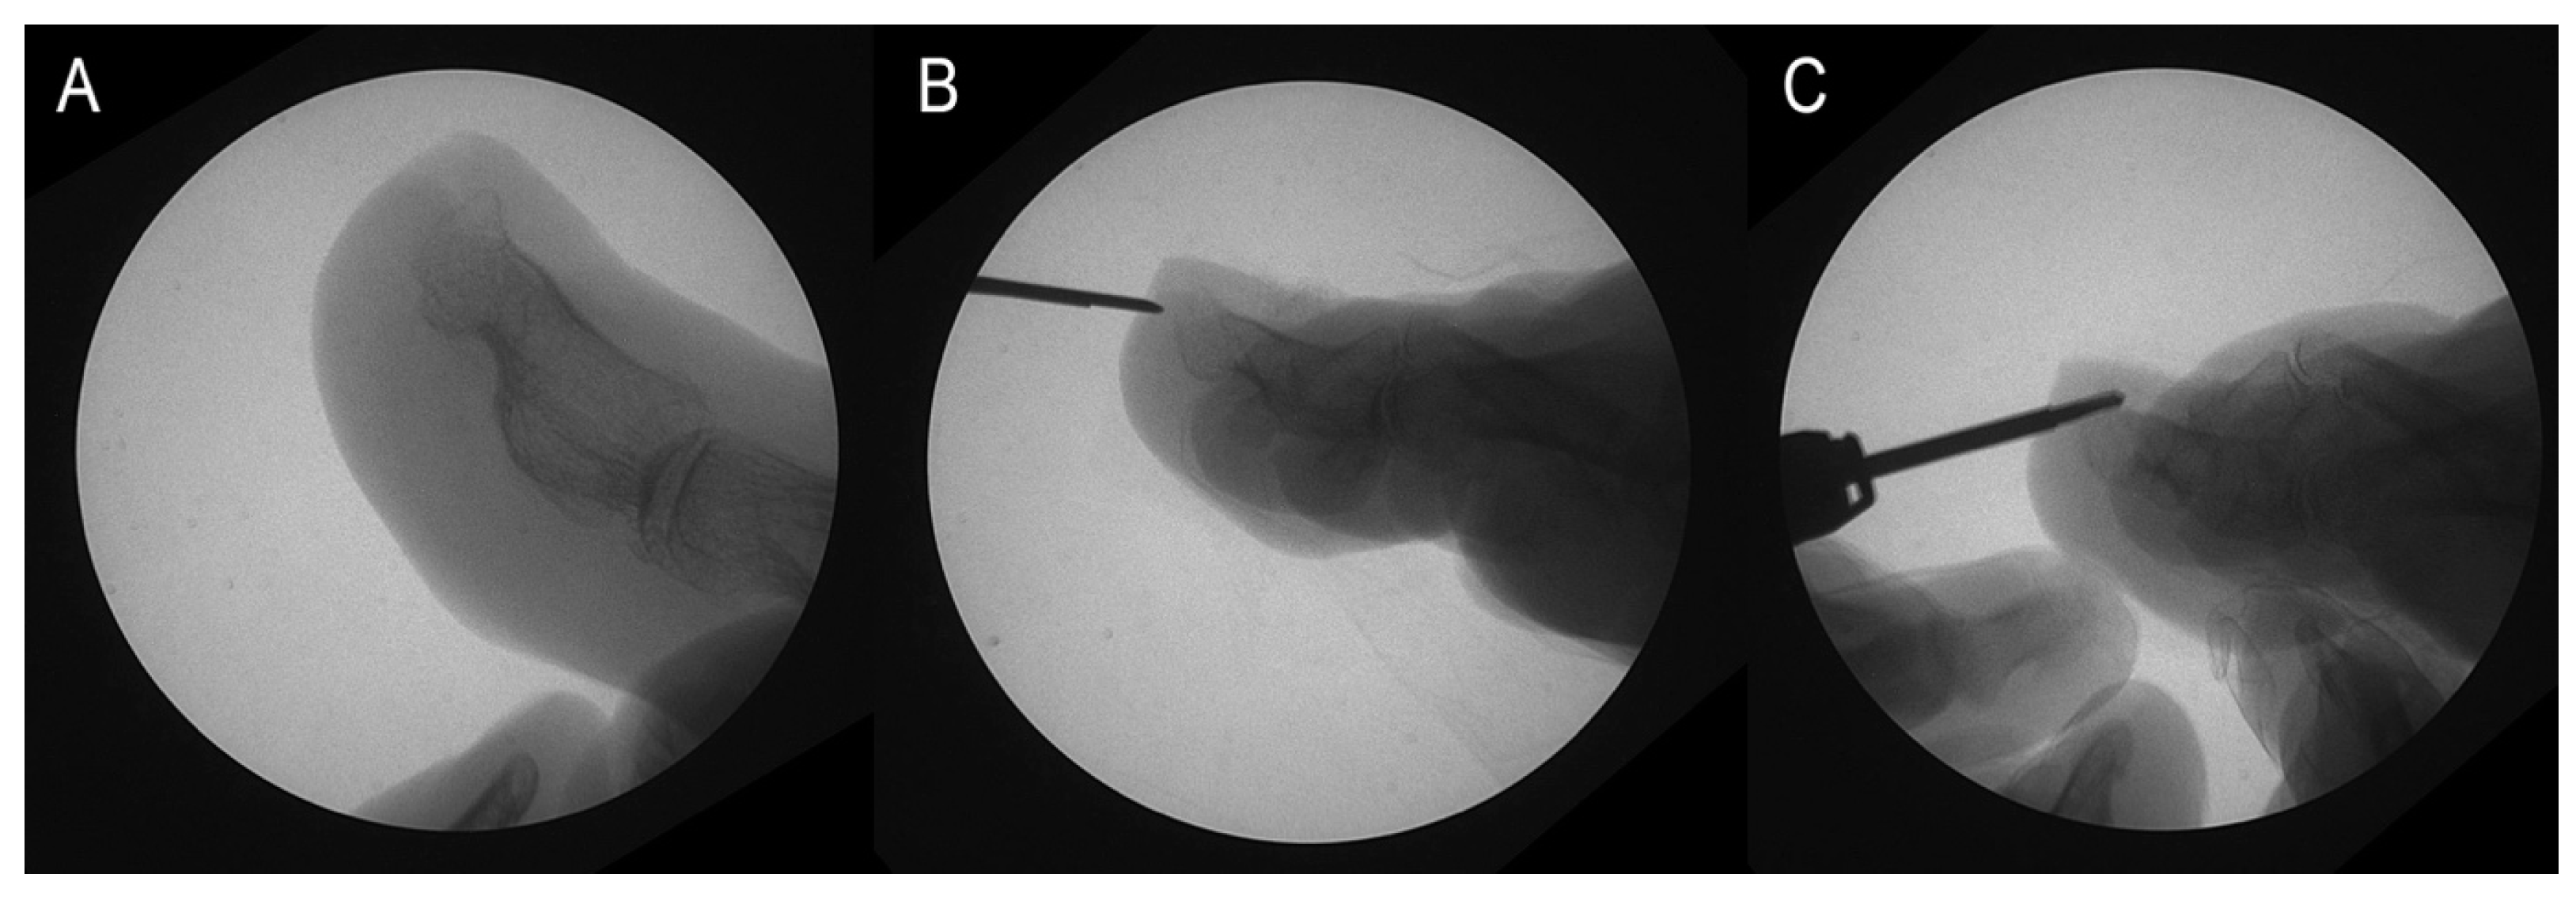

The surgery was performed according to the protocol outlined in [17] during the second visit, following these steps:

• A 2–4 mm incision was made using a Beaver-64-MIS scalpel on the distal surface wall of the toe, parallel to the longitudinal axis of the toe, followed by drilling of the osteophyte (Figure 2B).

• Osteotripsy was performed using medial and lateral movements of a mini-Shannon drill (Figure 2C).

Figure 2. Osteotripsy performance. (A) Surgical image. (B) Incision with no. 64 Beaver scalper. (C) Distal phalax osteotripsy.